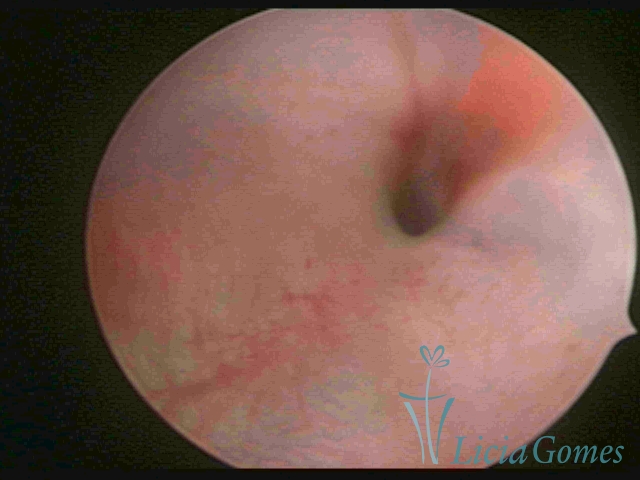

Third part or upper section

Presents the mucosa with a smooth, poorly vascularized surface, to the internal orifice